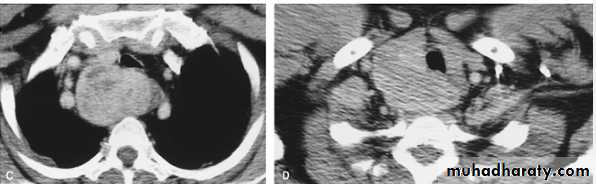

chest practice

Subpulmonary pleural effusion. On the (A) erect PA and (B) lateral radiograph the effusion simulates a high hemidiaphragm. (C) Ultrasound and (D) CT clearly show that the effusion is located above the diaphragm. Arrows = diaphragmatic area.